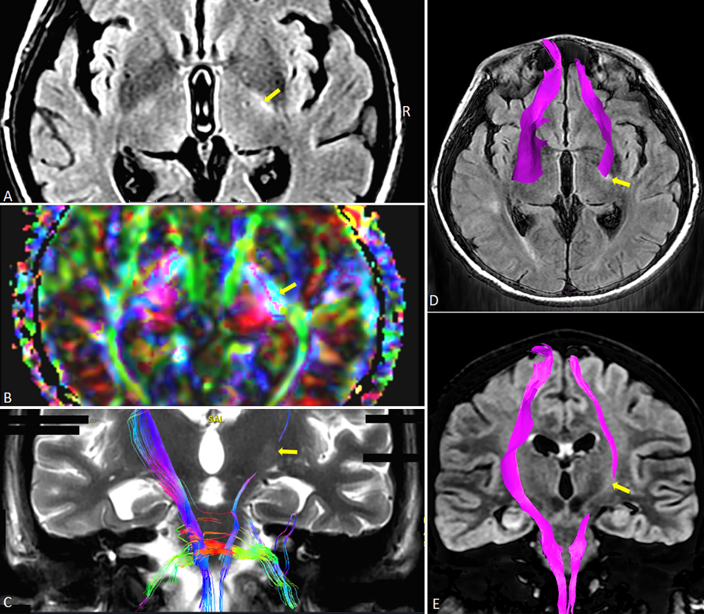

Neuro-imaging techniques like computerized tomography (for acute phase) and magnetic resonance images (in stable patients) are helpful to identify the anatomical place and the morphological structure of the injury and as in a case report from the literature, they often show diffuse axonal injury (3,6,10,12,21). Aside from these techniques, dysconnectivity in white matter; especially on the right posterior internal capsule, corpus callosum and the splenium shown on diffusion tensor imagings are associated with the early stages of PSH (2).

It should also keep in mind that other medical conditions related to trauma and intensive care treatments may also cause delays in diagnosing PSH, as in a case reported by ourselves (21). In this case report it was stated that a 26-year-old female suffering from TBI was admitted to the ICU with diffuse axonal injury and deep coma. Even though she had episodes of sympathetic activities at early admission she also had other medical problems like sepsis and acute hypoxemic respiratory failure at the same time. During her stay in the ICU her magnetic resonance images showed diffuse axonal injury (Figure 3) and the sympathetic symptoms re-occurred while there were no other contemporaneous medical problems. Since PSH-AM was applied. Her CFS was 13, DLT was 9 and she had a total PSH-AM score of 22 and diagnosed with PSH. The diagnostic tool PSH-AM can help the clinician diagnose and treat PSH at early stages, if it begins to be used from the admission of the patient unless there are no other concurrent pathologies.